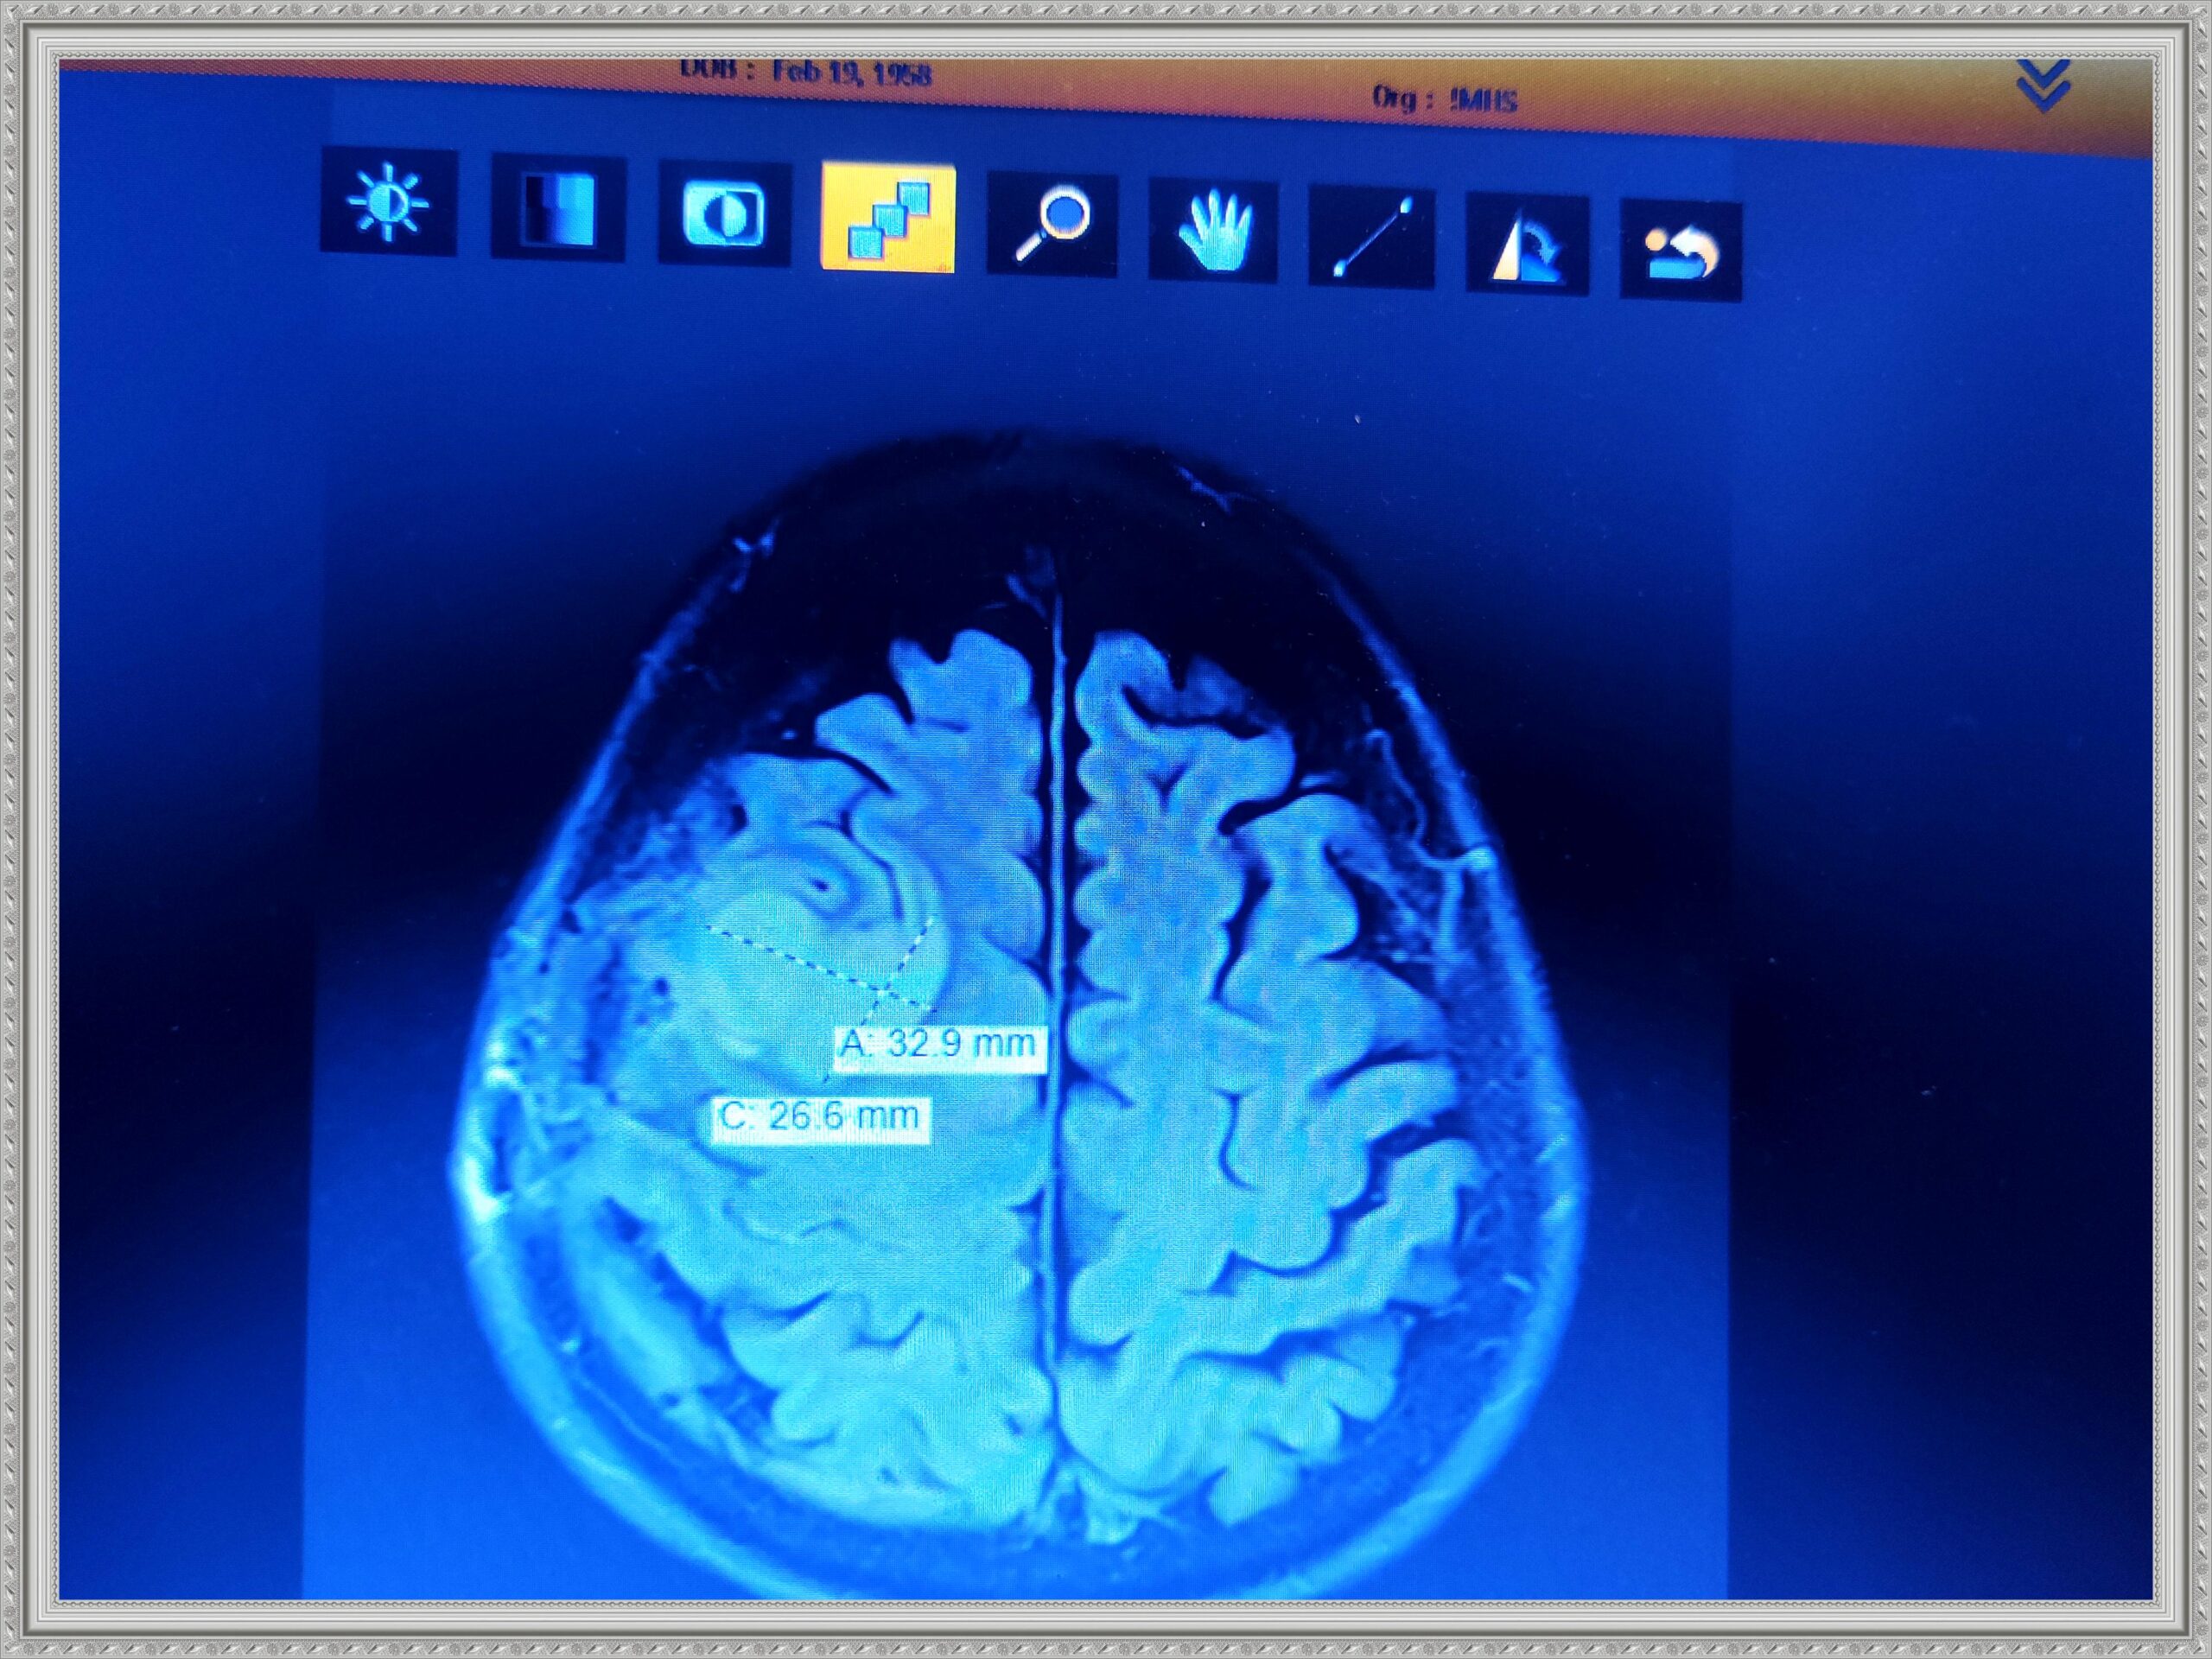

The next gallery shows me at Memorial Central Hospital in Colorado Springs after having surgery to remove my tumor and staying for a few weeks after for Physical, Speech and Occupational Therapy. The staff there was so AWESOME! I hold every one of them dear to my heart.